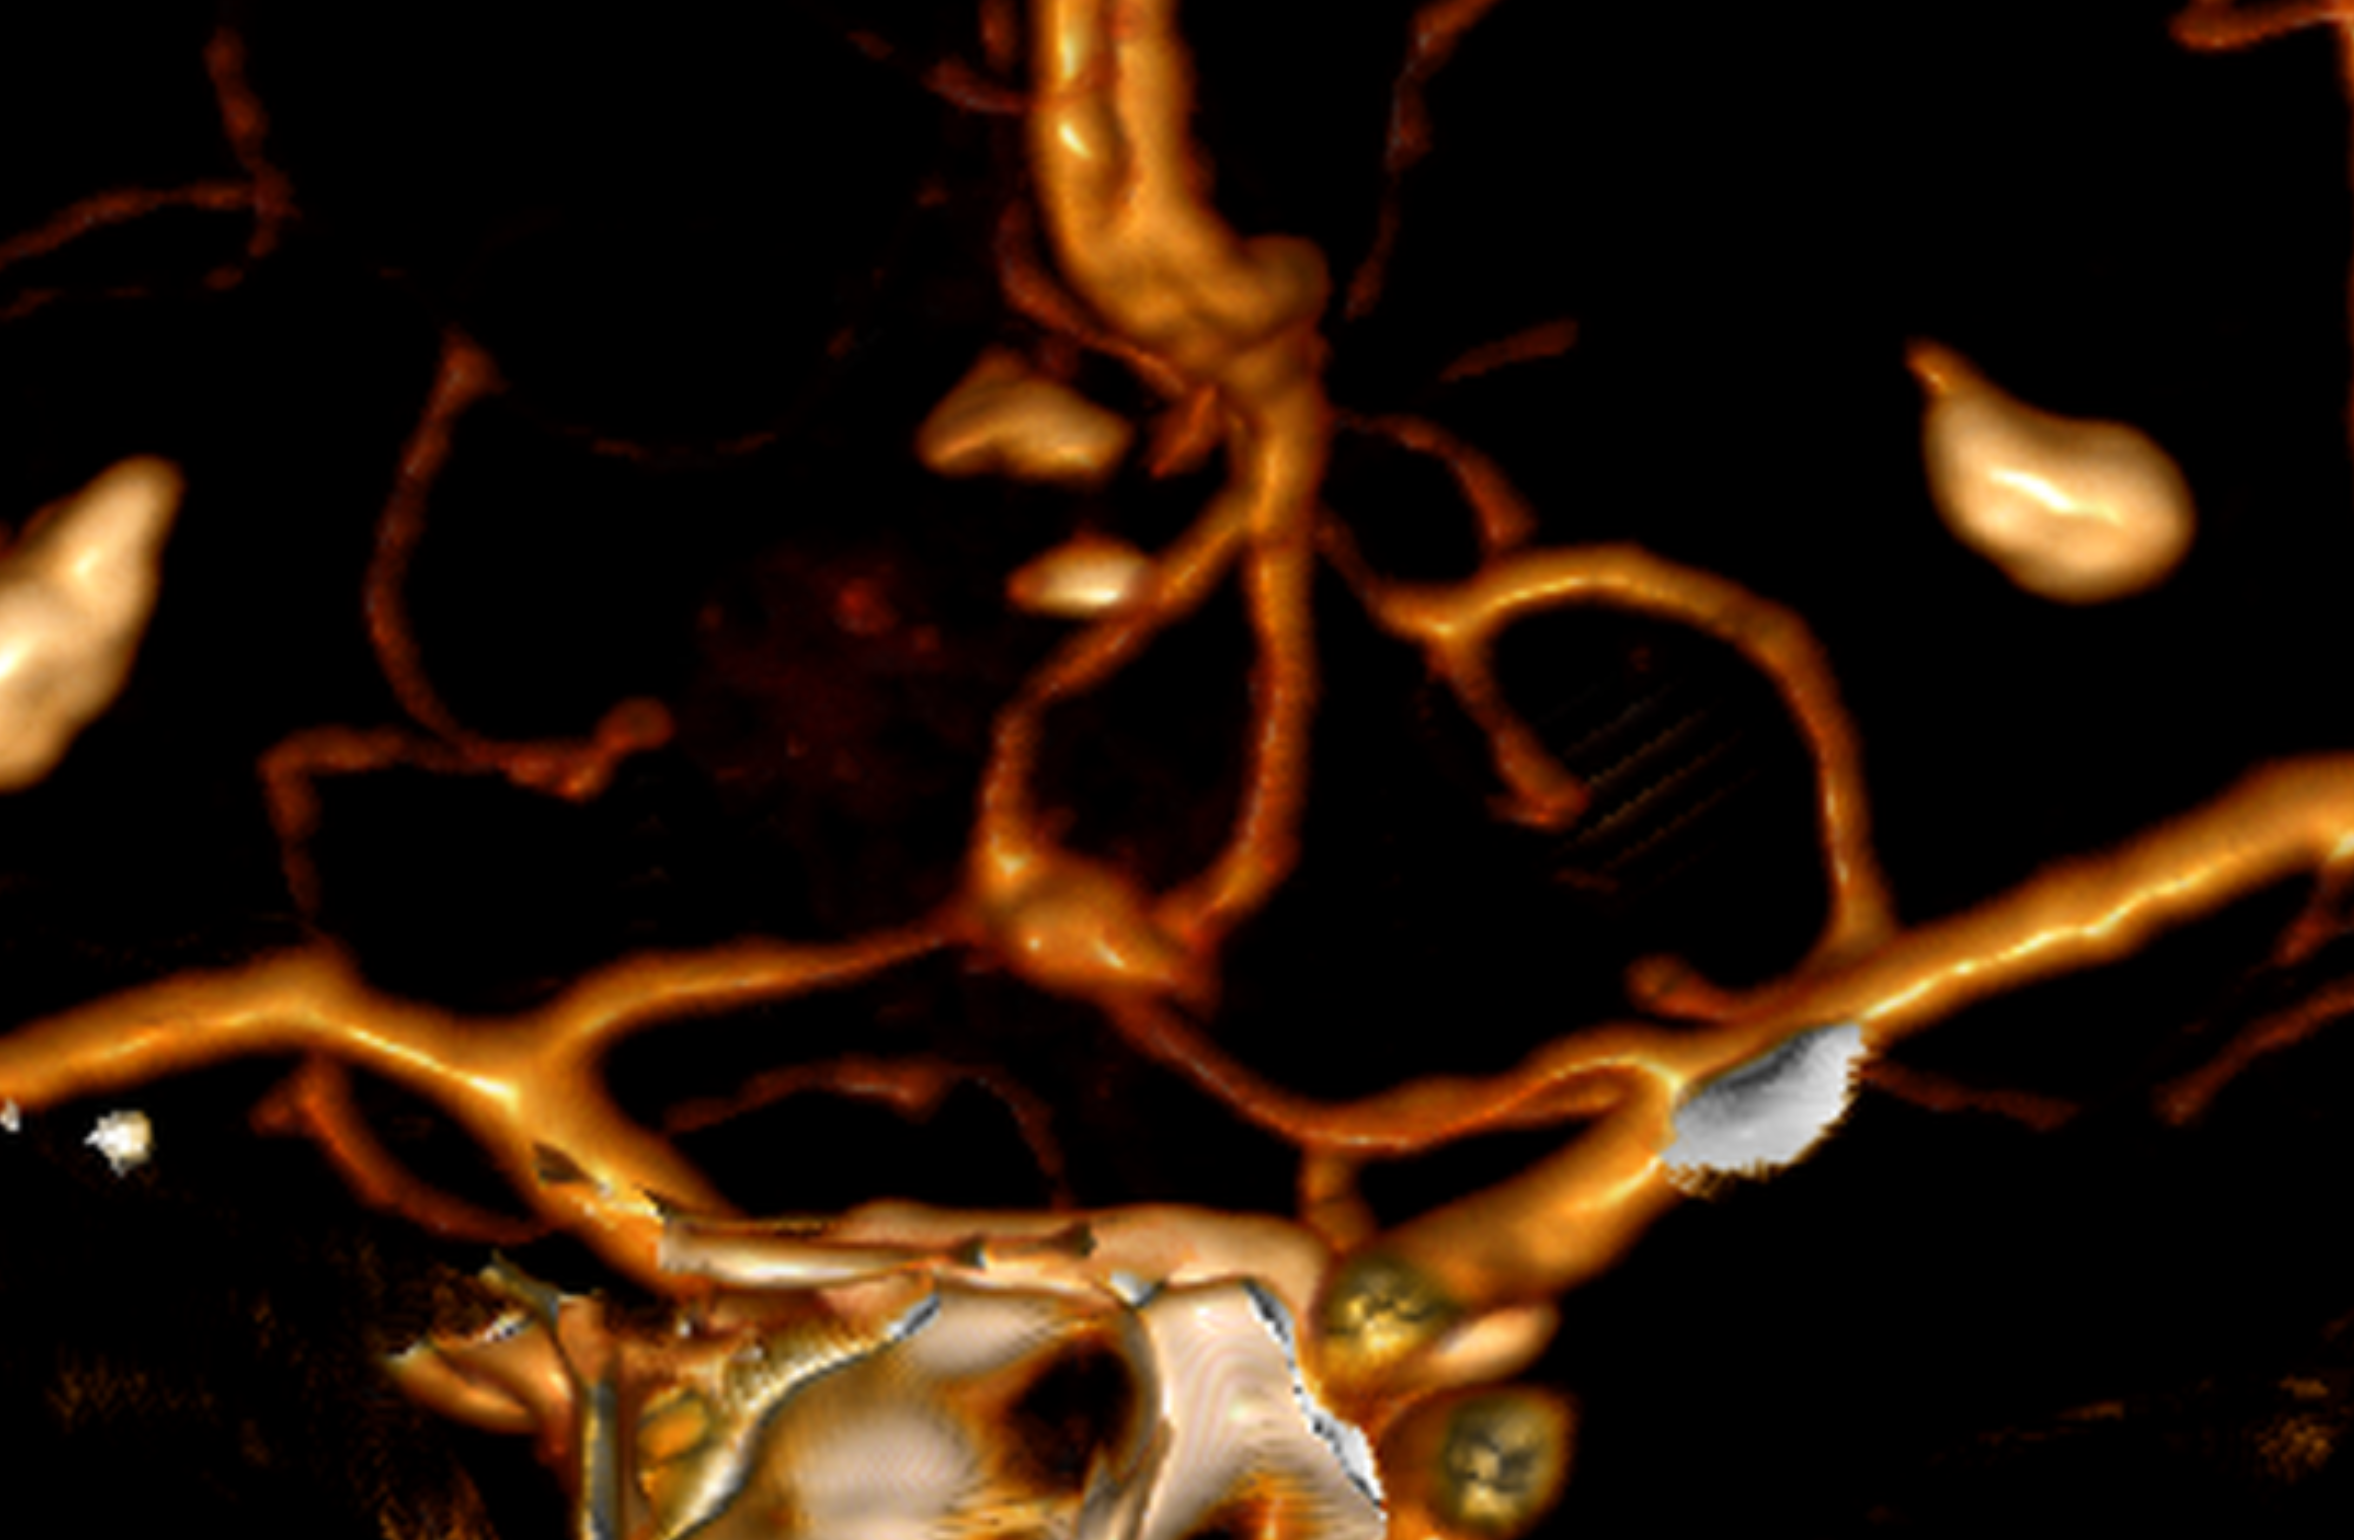

Se pueden usar varias modalidades de imagen para definir la MAV. La TC (Tomografía) y su variante Angiotomografía brindan información sobre la ubicación y la anatomía vascular estática, incluidos los vasos que irrigan y drenan la MAV. La resonancia magnética nos dice en qué parte del cerebro se encuentra la MAV y ayuda a medir el riesgo y los enfoques quirúrgicos y brinda información sobre hemorragias previas. La angiografía cerebral brinda información dinámica detallada sobre los patrones de flujo y el drenaje venoso. Es la prueba más sensible y poderosa, sin embargo, es técnicamente más «invasiva» y conlleva un riesgo muy pequeño de accidente cerebrovascular.

Angiografía cerebral 3D que muestra un aneurisma